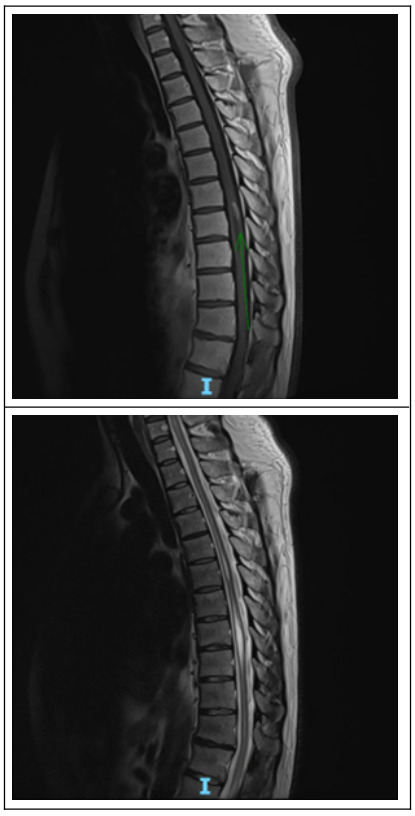

MRI of the brain showed scattered subcortical and periventricular FLAIR hyperintense lesions suggestive of demyelination. (Figure 1). Contrast-enhanced T1 did not show any lesions. Also, an MRI of the thoracic spine showed a syrinx from C5-T12 and patchy non-enhancing cervical cord signal changes with an intramedullary cord lesion at the level of T8 with linear enhancement. (Figure 2). An MRI of the brain revealed a few scattered subcortical and periventricular FLAIR hyperintense lesions as well as non-enhancing FLAIR hyperintense lesions in the anterior pontomedullary junction and left cerebellum. Laboratory workup revealed an elevated ESR, low methylmalonic acid, normal vitamin levels (B1, B6, B12, E), and negative infectious and autoimmune panels (e.g., ANA, dsDNA, viral studies). He was treated with high-dose intravenous methylprednisolone (250 mg every 6 hours for 5 days), gabapentin, and vitamin B12 supplementation. Ultimately, CSF analysis was positive for oligoclonal bands without cytologic abnormalities, confirming the diagnosis of MS. Neuromyelitis-optica gene and AQ4-IgG were negative. His neurological symptoms stabilized with therapy. Physical and occupational therapy were initiated, and the patient was discharged with outpatient neurology follow-up.

In this patient, the presence of a syrinx—a fluid-filled cavity within the spinal cord—posed a diagnostic challenge. Syrinx formations are typically associated with conditions like syringomyelia or Chiari malformations and are relatively uncommon in MS patients.4 A case by Waziri et al.5 reported syrinx formations associated with demyelination.5 Weier et al.6 reported a prevalence of 4.5% of the syrinx in MS, highlighting their rarity.6 This reinforces the importance of not dismissing clinical suspicion of MS solely based on such atypical imaging findings.